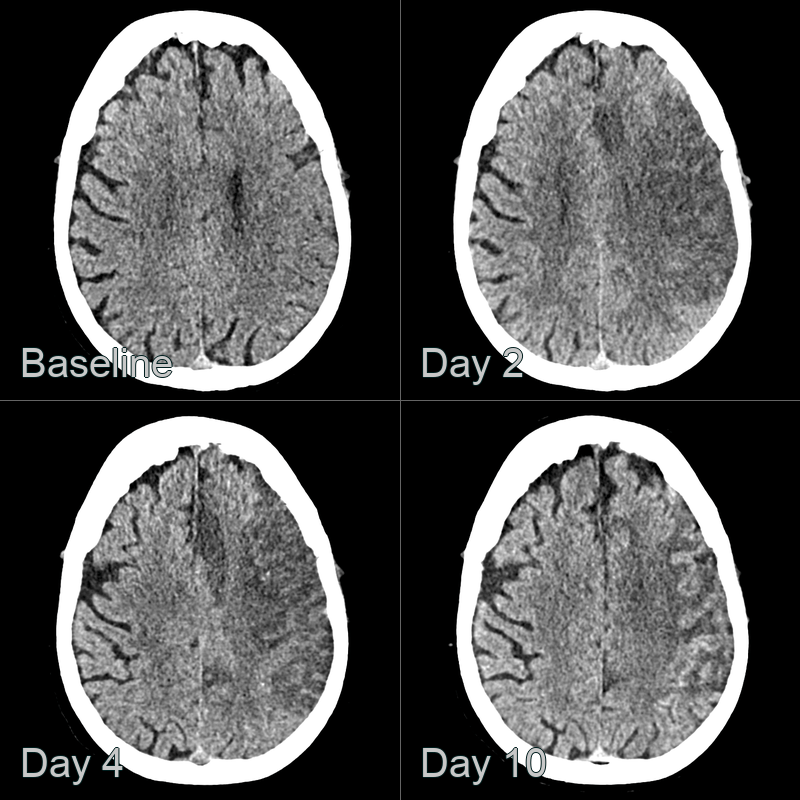

• A 50-year-old patient presented with right sided weakness.

• CT showed progressive hypoattenuation in the left MCA and ACA territory up to day 4.

• At day 10 post-admission, cortical hyperdensity (obsuring the ACA infarct) was consistent with cortical laminar necrosis.